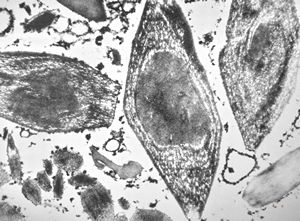

M, | crystalline inclusions in plasmocyte